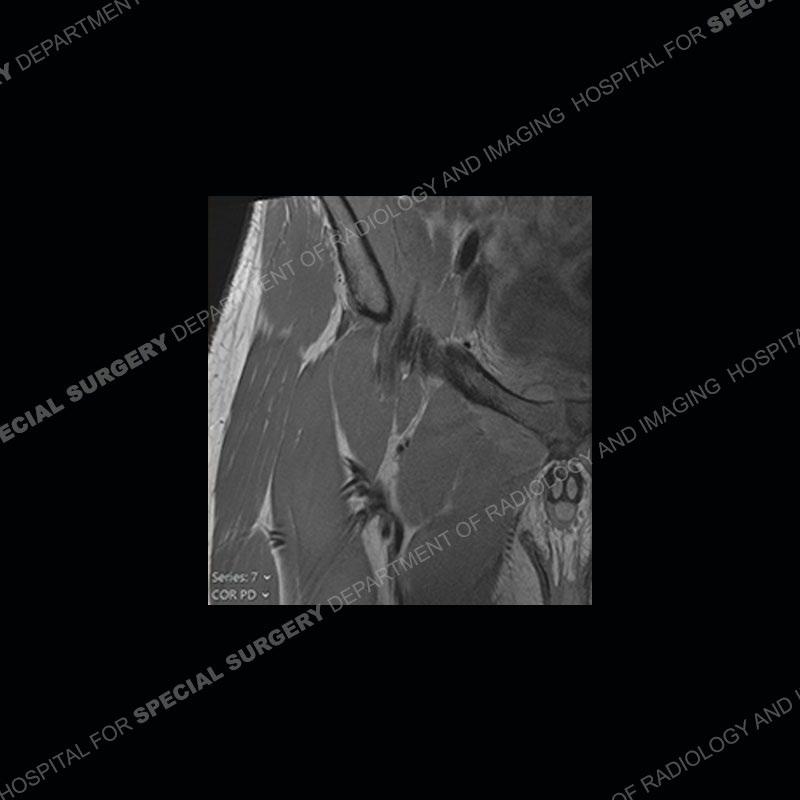

Radiographs did not demonstrate any clear abnormality. The MRI shows markedly abnormal signal of the right superior pubic ramus and abnormal signal/”mass” extending into the adjacent soft tissue. The inferior articular surface of the ramus showed what was thought to be bony destruction. CT examination shows a destructive process of the right superior pubic ramus.

Subsequent MRI in a very short time interval shows markedly increased abnormality of the ramus and increased edema and “mass” of the soft tissue. Post contrast imaging shows multiple, rim enhancing collections of the soft tissue and similar albeit less conspicuous enhancing collection of the ramus.

This case was a bit surprising to all involved given that the young man is otherwise in good health and extremely active in sports. The original thought was this case was going to be an overuse injury or stress fracture. The pubic ramus with the adjacent physis acts as a metaphyseal equivalent and although not frequently thought of would be a reasonable location for infection/osteomyelitis. The first MRI was somewhat confusing as the process did not have an appearance of a stress injury or rectus adductor aponeurosis injury. The degree of edema of the bone and soft tissue together would be odd especially for a sports hernia process. Initially, the thought was of an aggressive process which could be infection or neoplastic. Particularly, the abnormal architecture of the inferior surface of the ramus looked like a destructive process.

The repeat MRI, with the marked degree of increased abnormality of the bone and soft tissue shifted the diagnosis to a high degree towards infection. Even the most aggressive of neoplasms would not have that the degree of change in a 3-day time span. The CT study was shown before the repeat MRI but actually occurred just after the repeat MRI. It helped confirm the destructive process of the ramus and particularly the abnormal architecture along the inferior margin. The patient went on to have a CT guided aspiration of one of the soft tissue collections with 4cc of purulent fluid obtained. A surgical irrigation and debridement of the bone and soft tissue was performed. A PICC line was placed and the patient is currently undergoing IV antibiotic treatment with a possible repeat irrigation and debridement.